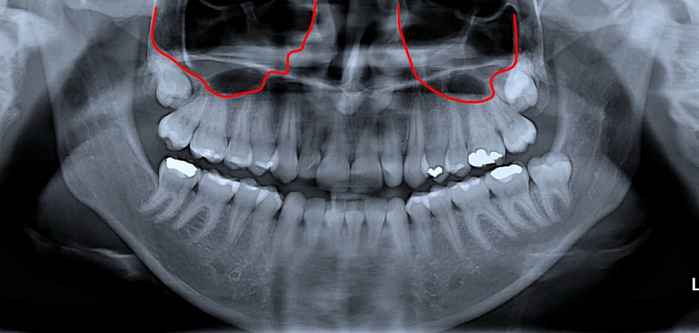

방사선 사진에서 표시해둔 부분이 상악동이라는 공기 주머니 입니다.

상악동은 코(nasal cavity)와 연결되어있습니다.

두개골의 중량감소, 목소리의 울림부여, 호흡된 흡기의 습도 증가, 흡기 중 발생된 내압의 차이를 감소시키는 등의 기능이 있습니다. 각설하고…

위턱의 사랑니와 상악동 사이의 뼈가 얇은 경우가 대부분이기 때문에, 사랑니를 뽑을 때 상악동의 뼈와 점막이 같이 제거되면서 입안과 상악동이 연결되는 경우가 생깁니다.

이것을 ‘상악동 천공’이라고 합니다.